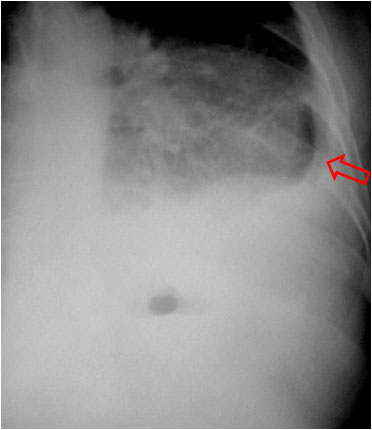

Cuando en una radiografía de tórax se ve un nivel hidraéreo hay que establecer la diferencia entre intrapulmonar (absceso, quiste, tumor cavitado) o extrapulmonar (derrame encapsulado, empiema). La ausencia de la pared superior de una colección intratorácica con nivel hidroaéreo, en al menos una de las dos proyecciones de tórax, es un signo que permite diferenciar el encapsulado pleural de cavidades de localización intrapulmonar.

En las imágenes vemos un nivel hidroaéreo en hemitórax derecho (flechas rojas) sin que sea visible la pared de la cavidad. Se trata por tanto de una colección extrapulmonar.